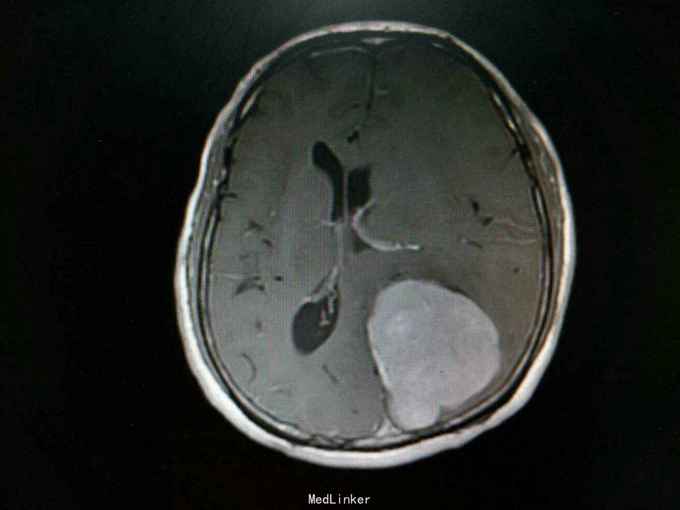

查体:生命体征平稳,神经系统检查未见明显异常。辅助检查:头颅增强+血管MR扫描提示:双侧额顶叶、侧脑室周围见斑片状异常信号区,T1WI呈等信号,T2WI及T2-FLAIR呈稍高信号。左侧枕部大脑镰旁可见团状软组织肿块影,边界清,形态不规则,呈分叶状,大小约62mm×49mm。病灶T1WI呈等信号,T2WI呈稍低信号,周围可见脑脊液环绕;增强扫描病灶明显均匀强化。病灶占位效应较明显,左侧顶枕叶脑实质受压向内移位,左侧侧脑室受压变形。中线结构稍向右移位。余脑实质未见异常信号灶。颅骨未见明确异常。头颅MRA:病灶内可见多发迂曲血管影,可见大脑后动脉及脑膜动脉供血。双侧大脑前、中、后动脉管壁光滑,走行自然,管腔未见明显扩张或狭窄,未见动脉瘤征象。Willis环未见异常。1. 左侧枕部大脑镰旁占位性病变,考虑脑膜瘤可能性大;2. 轻度脑白质疏松;2. 头颅MRA提示病灶血供来自左侧大脑后动脉及脑膜动脉;余未见异常。

诊断:左枕部大脑镰旁脑膜瘤 处理:左枕部开颅大脑镰旁脑膜瘤切除术

术后病理提示:(左顶枕叶肿瘤)脑膜瘤,上皮型,WHOⅠ级。大脑镰旁脑膜瘤是指位于大脑纵裂并与大脑镰相连的一类临床上常见的脑膜瘤,常突入一侧大脑半球内,有时可向双侧发展。也有少数肿瘤呈扁平型,在大脑镰内浸润性生长。肿瘤可由大脑镰脑膜动脉供血,也可由脑内动脉供血,其前部可来自眼动脉分支,后部来自枕动脉,中部可有脑膜中动脉供血。在肿瘤基底和附近的大脑镰内有多条扩张的静脉。